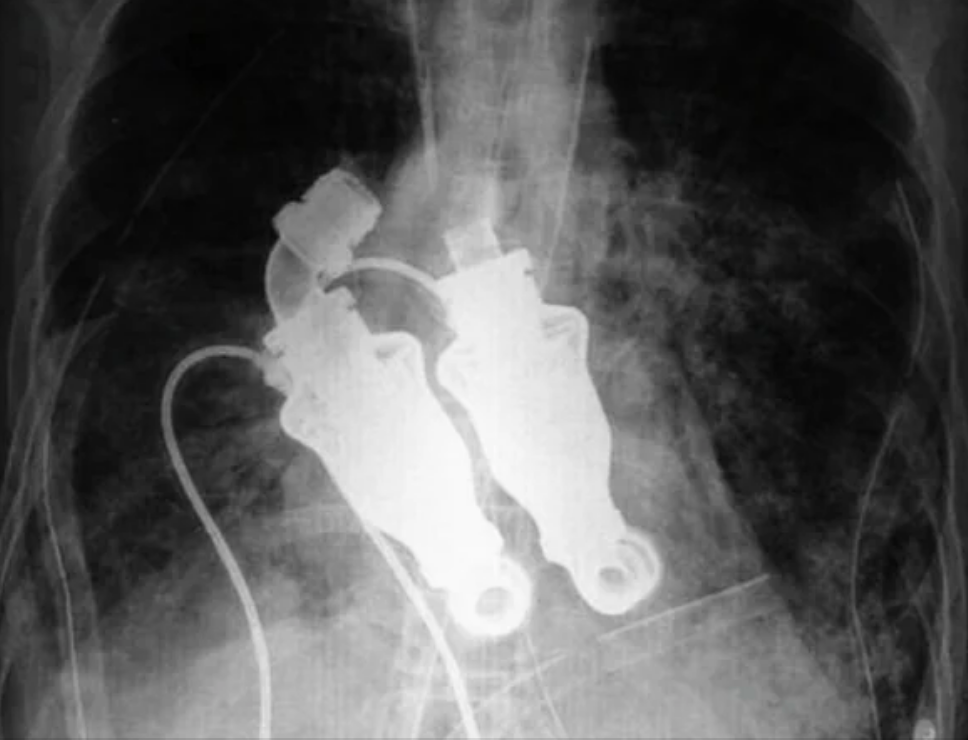

8.Another medical advancement? This manhada device implanted into his chest that functioned as his heart, which allowed him to live for five weeks after receiving it, rather than dying immediately. With the device, he had no heartbeat.